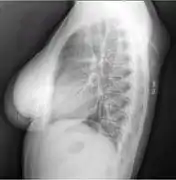

A physical exam is typically the easiest way to diagnose it. Rarely, a tissue biopsy or imaging may be required. The imaging modality of choice is magnetic resonance imaging (MRI), because it has superior sensitivity of distinguishing it from liposarcoma as well as mapping the surrounding anatomy.[20]

X-ray of a lipoma

X-ray showing lipoma